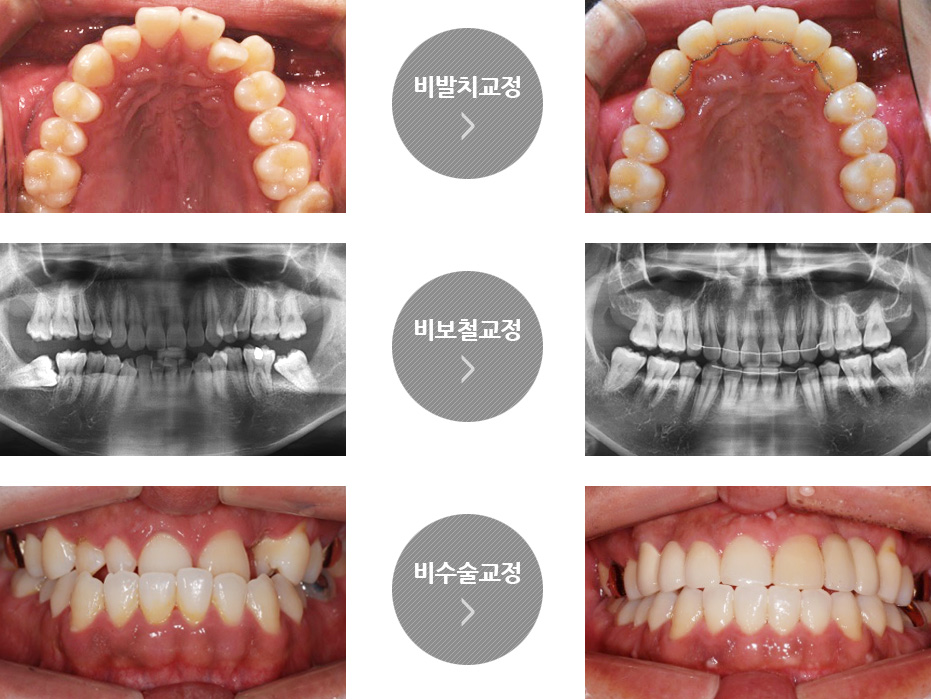

고운미소치과 목동점은 중등도 이하의 골격 부조화로 인한 불규칙한 치열과 부정교합 증상을 가지고 계신 환자 분의 자연 치아를

최대한 유지하고, 부담스러운 양악수술 대신 정상교합을 찾을 수 있는 비발치/ 비보철/ 비수술 원칙을 통해 교정 치료를 진행합니다.

고운미소치과 목동점은 가급적 발치를 하지 않고 자연치아는 최대한 살리면서 치열을 고르게 배열하려는 원칙을

가지고 있습니다. 많은 병원에서 간단한 부정교합이 아닌 이상 대부분 발치 교정으로 진행하는데, 이제는 의술의

발전으로 과거에 비해 발치 없이 치아교정이 가능한 경우가 늘어나고 있습니다. 풍부한 노하우를 가진 교정의사의

정확한 진단 하에, 발치없이 가지런한 치열, 자연스러운 입술 외모를 비발치 교정을 통해 얻을 수 있습니다.